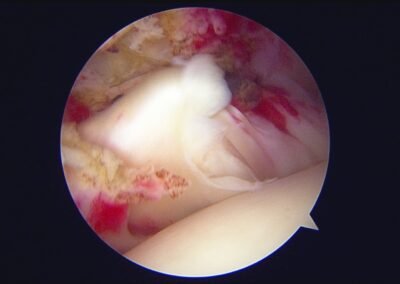

GalleryShoulder rotator cuff repair Meniscus root repair Meniscus repair Bankart repair for recurrent shoulder dislocation ACL reconstruction Machines Instruments